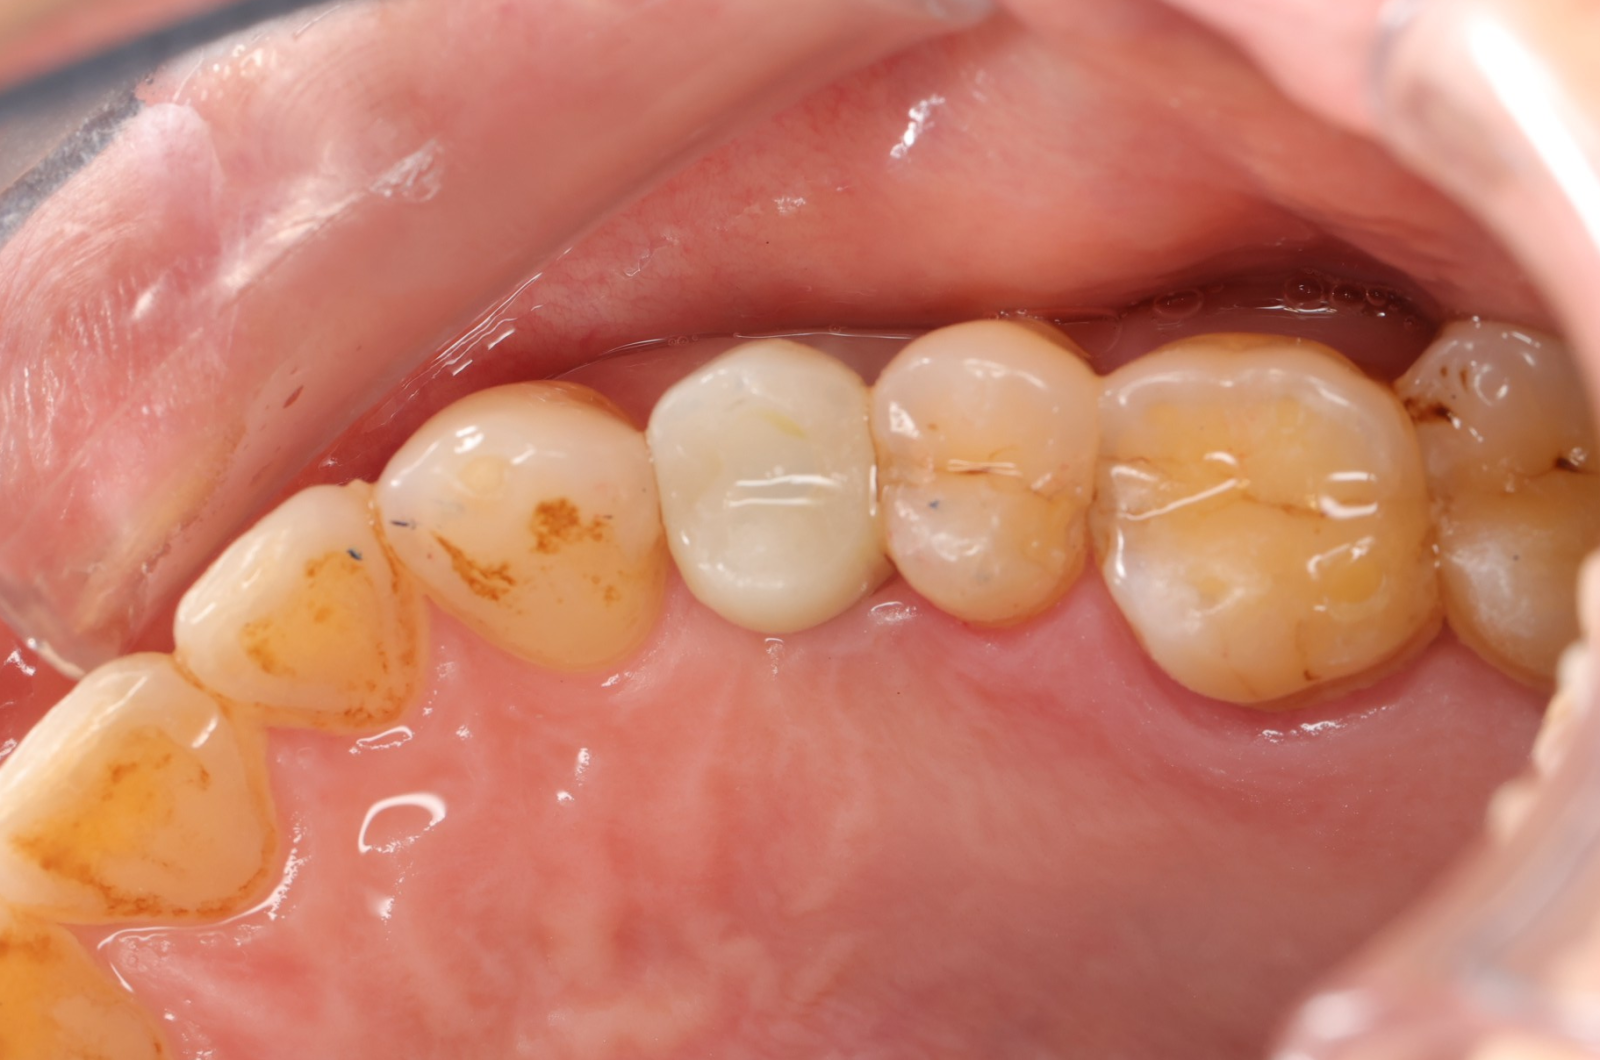

- 手術過程,在植入植體前先用導板定位,確認植牙位置及角度。使用導板讓傷口範圍縮小。

- 手術後傷口小無需縫合,也不用再來拆線,幾乎不會腫脹出血,術後恢復期舒適快速!

- 待3.4個月後裝上全陶瓷牙冠完成植牙療程。整個療程過程輕鬆。